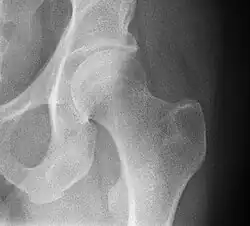

Superficies articulares

Está formada por una superficie cóncava que es el acetábulo y otra convexa, la cabeza femoral, por ello la articulación tiene una gran movilidad.

- Acetábulo o cavidad cotiloidea del coxal: ubicada en la cara externa del hueso, presenta una parte articular en forma de medialuna y una parte no articular que es el trasfondo de la cavidad. Está circunscrita por la ceja cotiloidea, en su borde inferior está interrumpida por la escotadura isquiopubiana. La cavidad cotiloidea está orientada hacia abajo y hacia delante.

- Cabeza femoral: fr superficie convexa, corresponde a dos tercios de esfera. En su centro presenta la fosita del ligamento redondo para la inserción de dicho ligamento. La cabeza femoral se mantiene unida a la diáfisis a través del cuello femoral, el cual está orientado hacia arriba, adentro y adelante.

- Coxa valga. El ángulo formado por el cuello del fémur y la porción larga del hueso (diáfisis) está aumentado, generalmente por encima de los 135° en adultos.[13]

- Coxa vara. El ángulo formado por el cuello del fémur y la porción larga del hueso (diáfisis) está disminuido, generalmente por debajo de los 125.º en adultos.[13]